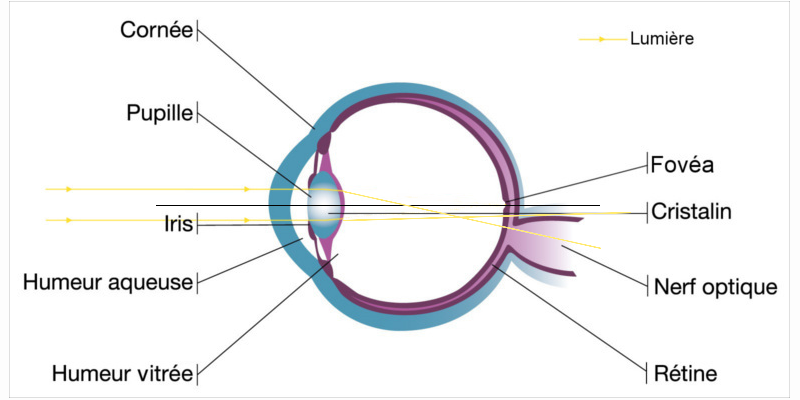

L’œil est composé de deux organes qui sont responsables de la réfraction de la lumière, c'est-à-dire responsables de notre bonne vision, à savoir la cornée et le cristallin.

Ces deux parties de l’œil sont censées être sphériques pour que la puissance soit la même partout. Cependant cela reste théorique car dans la pratique la puissance de l’œil est rarement la même partout et il se peut que le rayon de courbure soit plus important dans certaines partie de l’œil.

Si l’œil a une légère déformation au niveau de la cornée ou du cristallin, cela va engendrer ce que l’on appelle un cylindre, et c’est pour cela que les patients atteints d’astigmatisme ont besoin d'un cylindre avec un axe dans leur correction pour corriger ce défaut.